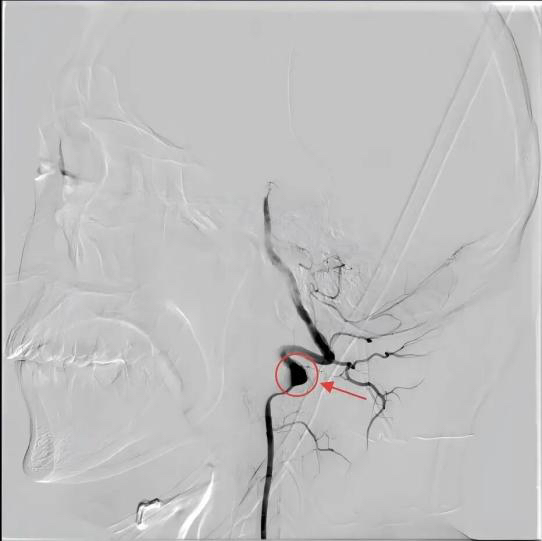

近日,江苏省人民医院(南京医科大学第一附属医院 江苏省妇幼保健院)神经内科接诊了一位经历两次中风的年轻患者。28岁的于先生(化名)热爱运动、自认身体健康,两个月前,在一次打完篮球后,突发右侧肢体无力、不能言语。经检查,医生发现其左侧椎动脉V3段夹层动脉瘤,基底动脉闭塞,随即进行基底动脉闭塞机械取栓术。术后血管恢复通畅,功能基本康复。

夹层动脉瘤

可年轻人为何屡屡中招?江苏省人民医院神经内科黄琳副主任医师指出:剧烈运动时,头颈部的快速扭转或过度后仰,可能使椎动脉等颈部血管内膜“撕裂”,血液通过撕裂口进入血管壁形成动脉夹层。若积聚的血液使血管壁在中层与外层之间发生剥离,形成一个假性腔隙并从椎动脉壁向外膨出,最终就会呈现为椎动脉夹层动脉瘤样扩张,随时可能引发血栓或血管破裂。同时,剧烈运动时血压骤升,血流冲击加剧,可能使血管内不稳定斑块破裂,瞬间触发血栓形成,堵塞关键脑血管。